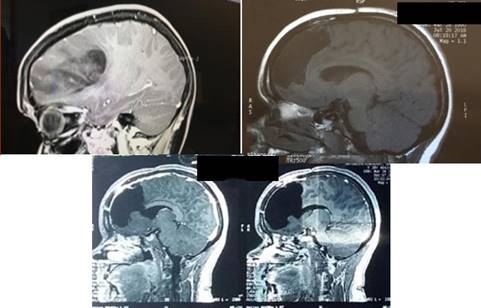

Figura 8: Glioma de bajo grado fronto-témporo insular izquierdo. Resonancia Magnética donde se observa la lesión trilobular.